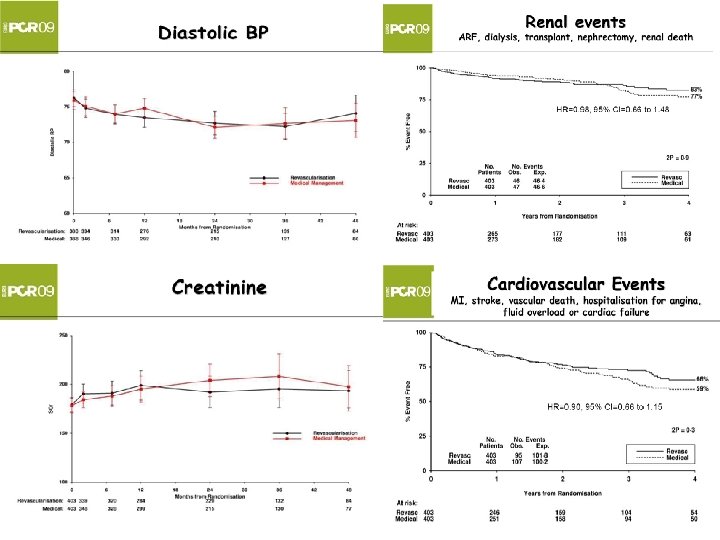

ASTRAL исследование Почти все данные сопоставимы…. . Но осложнения связанные с операциями? !

ASTRAL исследование Почти все данные сопоставимы…. . Но осложнения связанные с операциями? !

Нет доказательства по почечной функции преимущества ангиопластики почечной артерии против медицинской терапии Нет доказательства по вторичным точкам : АД, почечные события, большие сердечнососудистые события, смертность преимущества ангиопластики почечной артерии против медицинской терапии Нет доказательства по любым субгруппам

Нет доказательства по почечной функции преимущества ангиопластики почечной артерии против медицинской терапии Нет доказательства по вторичным точкам : АД, почечные события, большие сердечнососудистые события, смертность преимущества ангиопластики почечной артерии против медицинской терапии Нет доказательства по любым субгруппам